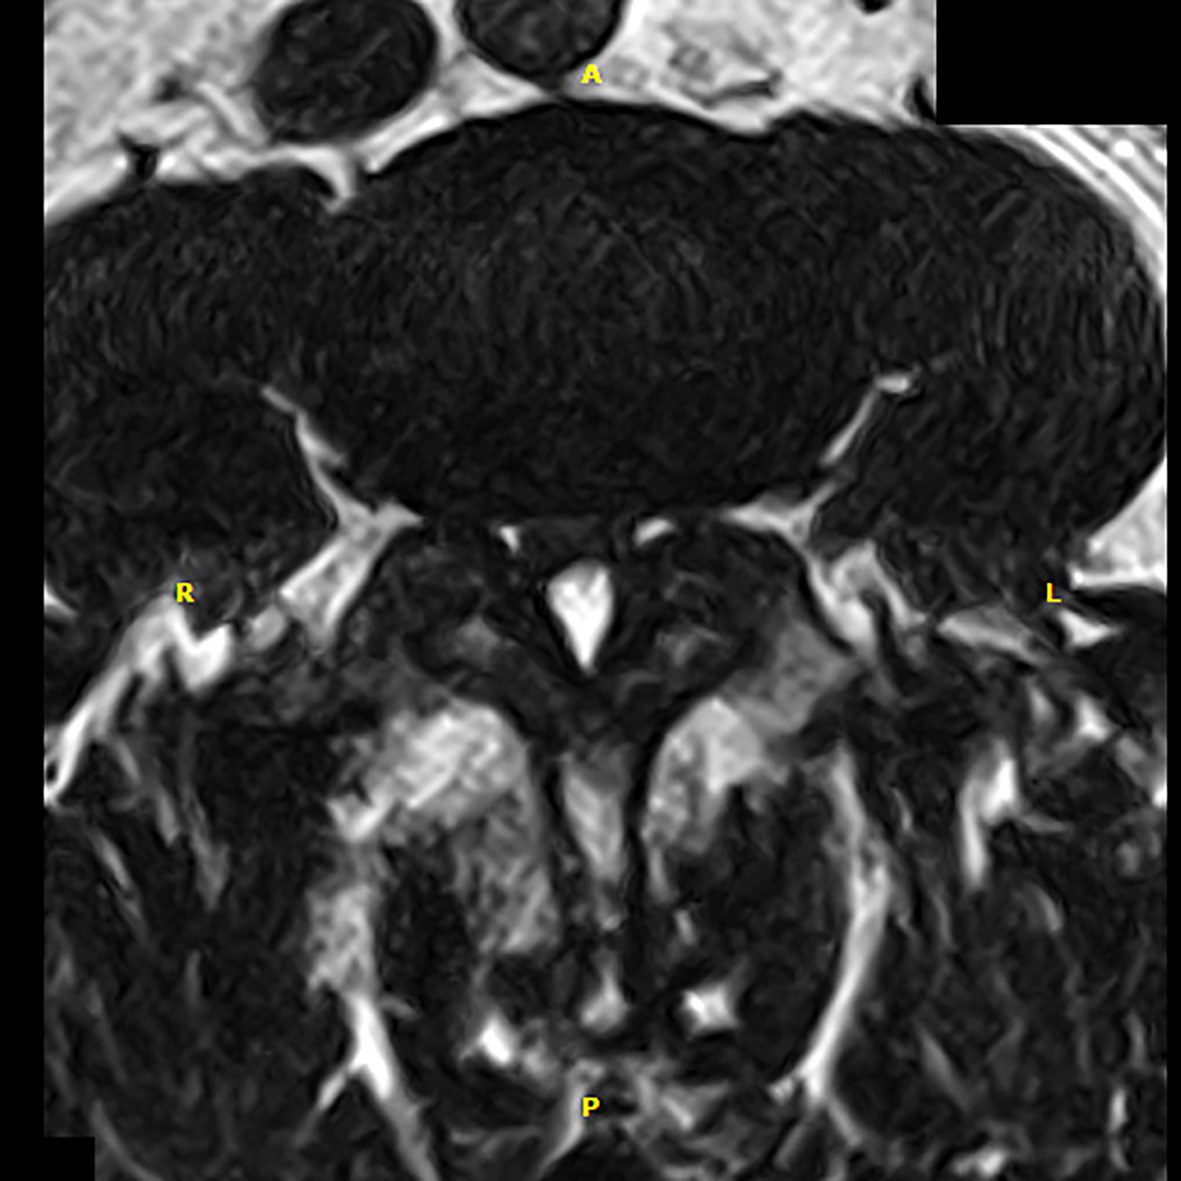

■ G-scan brio je revolučným systémom pre všetky muskuloskeletálne aplikácie od jednoduchej aplikácie na koleno až po aplikáciu na váhonosných častiach chrbtice. Predstavuje budúcnosť v muskuloskeletálnom MRI, pretože ponúka ďalšie diagnostické možnosti. V skutočnosti vďaka svojmu unikátnemu nakláňajúcemu dizajnu je možné pacienta posunúť do skutočnej váhonosnej pozície, čo vám umožní vizualizovať skutočný stav patológií

■ Váhonosnosť: vizualizácia stavu buď v klinostatickej pozícii (poležiačky) alebo v ortostatickej polohe (váhonosnej)